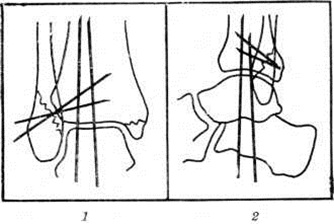

Для профилактики вторичного смещения в гипсовой повязке А. В. Каплан (1967) предложил метод трансартикулярной фиксации стопы и закрытый (чрескожный) остеосинтез спицами, заключающийся в том, что после ручной репозиции и наложения гипсовой повязки через окна в ней спицами Киршнера фиксируют голеностопный сустав, костные отломки и межберцовый синдесмоз (рисунок 3). Через 4—5 недель спицы удаляют, а гипсовую повязку оставляют на срок, необходимый для полной консолидации перелома.